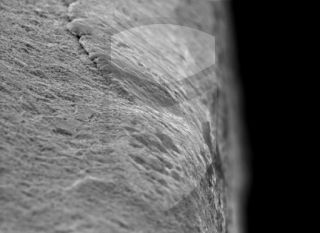

Implante 5 estrelas. Boa usinagem, algumas poucas rebarbas e ótima limpeza.

Topografia/rugosidade:

Marca e tipo de microscópio:

Jeol JSM 6390 Lv